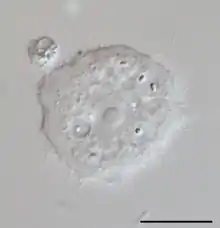

In cases of keratitis, diagnosis is typically achieved through evaluation of corneal scrapings. Scrapings are taking from the cornea, and plated on agar for culture, and also can be stained using Gram stain and Giemsa stain to differentiate between bacterial keratitis and AK. To culture Acanthamoeba, scrapings are placed on a non-nutrient agar saline plate seeded with a gram-negative bacteria such as E. coli. If Acanthamoeba are present, they will reproduce readily and become visible on the plate under 10–20 times objective on an inverted microscope. Polymerase chain reaction (PCR) can be used to confirm a diagnosis of Acanthamoeba keratitis, especially when contact lenses are not involved.[22] Confocal microscopy is a non-invasive technique that allows visualization of Acanthamoeba in vivo in cases in which corneal scraping, culture, and cytology do not yield a diagnosis.[23]